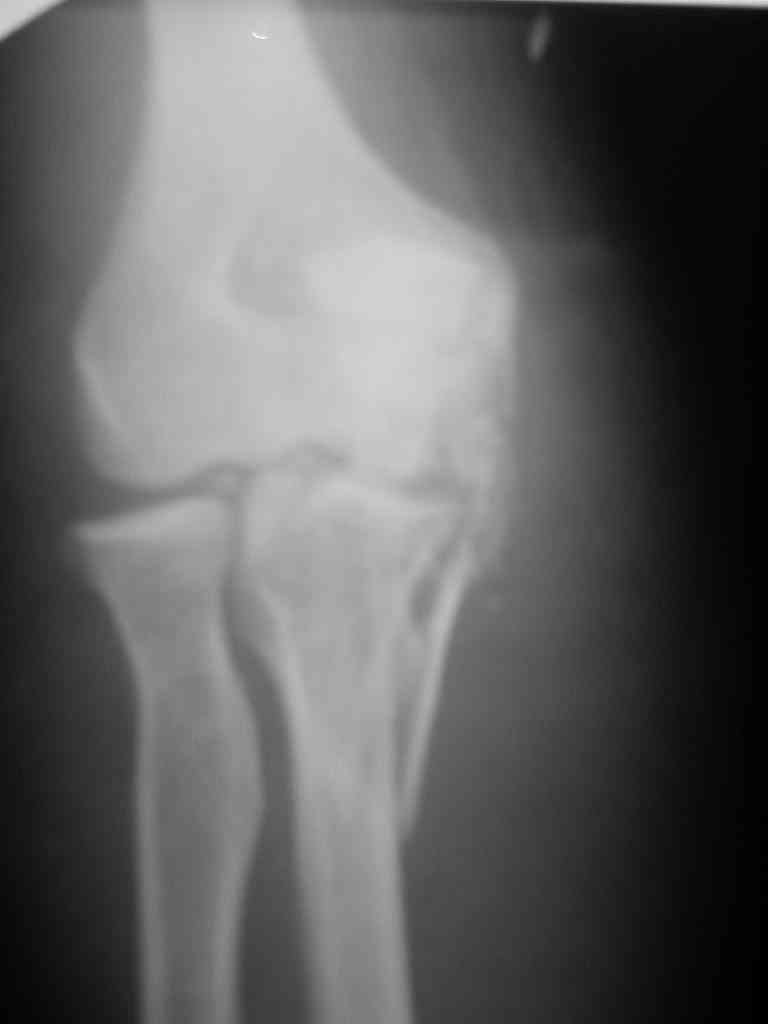

При самом большом к Вам уважении, Сергей Анатольевич, не соглашусь. У меня, после того, как добавили "прямой" снимок, сомнений не осталось. Венечный сломан наверняка. Но чтобы судить, насколько это критично для стабильности, нужно иметь строго боковую проекцию. И при этом помнить, что на него крепятся медиальные связки.

Прикрепляю снимок, где обведен фрагмент, несущий на себе венечный отросток (весь он смещён с этим фрагментом или частично - без качественной боковой проекции судить сложно), и отдельно на снимке обведено "ложе", от которого он сместился.

Как минимум два фрагмента, включающих суставную поверхность, и много (т.е. более двух) околосуставных осколков метафиза